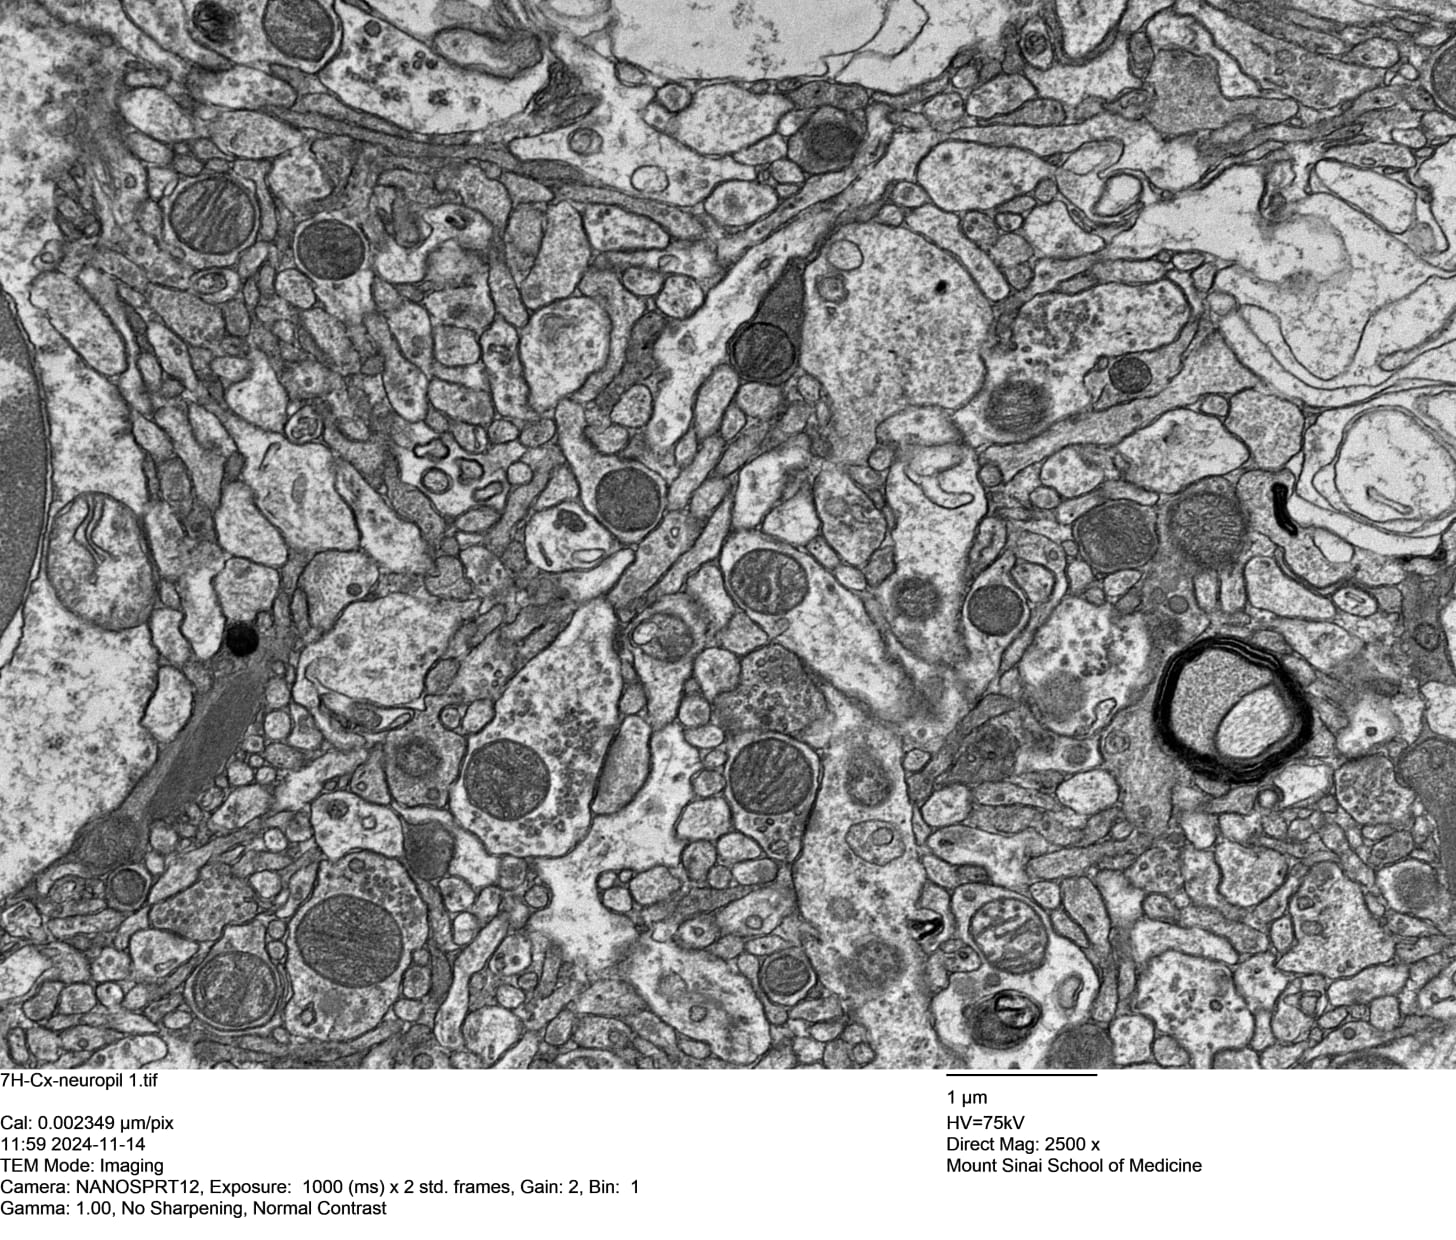

An example of a human brain sample preserved by fixation is shown in Figure 2. This image is from a donated human brain, preserved at SBP with current methods, after 4.5 hours of warm ischemia. The image was saved at approximately 4,000 x 3,000 pixels resolution but when you view it here, probably it will have been downsampled by Substack. It appeared originally in a paper archived by the National Library of Medicine at

https://pubmed.ncbi.nlm.nih.gov/40567433/

Figure 2. Sample of a human brain perfused with aldehyde.

If fixation is applied more promptly, it can lead to even better ultrastructural preservation quality. But if a significant delay occurs, this does not necessarily mean that a case will be refused. “We’re not saying that the quality is good in delayed cases,” Jordan Sparks comments, “just that it’s always better than with cryopreservation.”